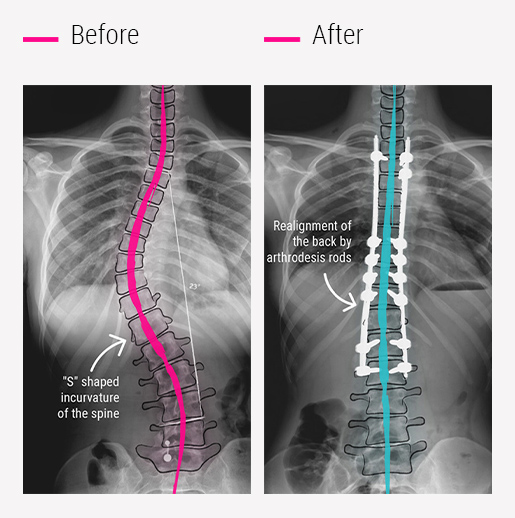

Spine deformity surgery is performed under O-Arm navigation guidance for accuracy and Neuro-Monitoring to avoid any neurological damage and to give best possible correction.